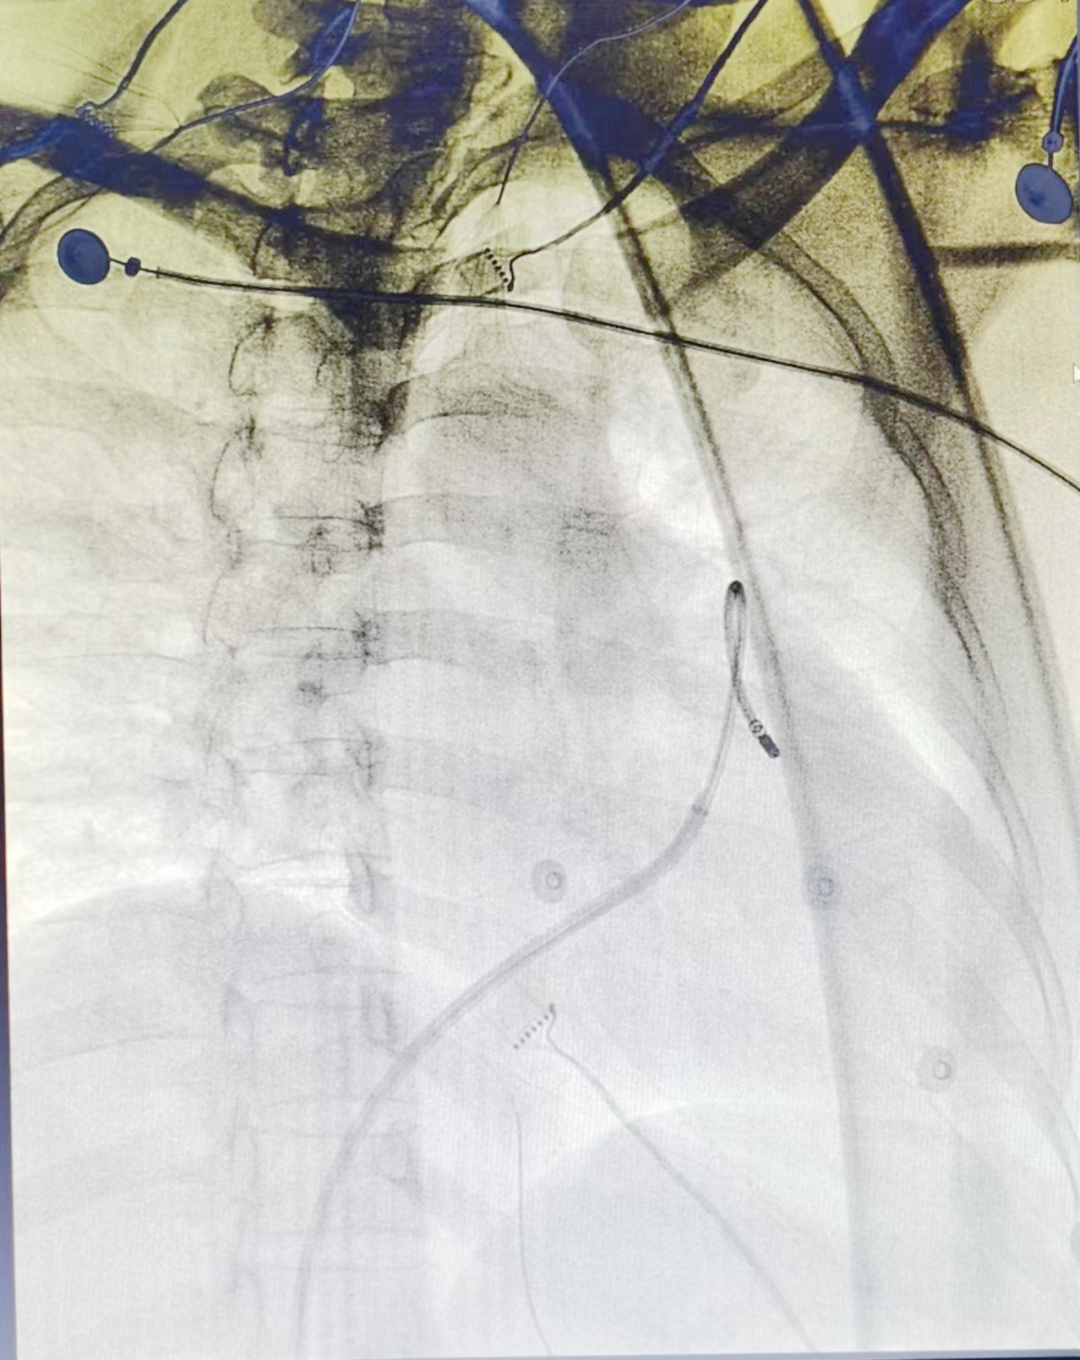

经过充分的术前准备,在广东省人民医院廖自立博士指导下,由张进鹏副主任医师、张惠琪主任医师、唐亮副主任医师为患者实施了心脏射频消融术,术中电生理检查明确肺动脉左窦瓣下起源的室性早搏,于靶点处消融5秒后室早消失,反复诱发未再发作,手术非常成功。术后患者无特殊不适,24小时内出院。门诊复查动态心电图示:偶发二形室性早搏,室性早搏6个,有两种形态,占总心搏<1%。

术中二维靶点图

术中三维靶点图